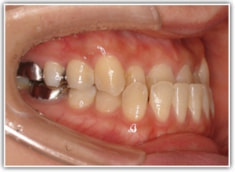

反対咬合ケース

治療法:表の矯正(T21ブラケット)

治療後(1年6ヶ月後)